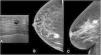

We included patients with histologically confirmed nonpalpable malignant lesions treated by surgery in 2015 or 2016. Patients were randomly assigned to presurgical marking with metallic clips (Group A) or with 125I seeds (Group B). In both groups, marking was guided by ultrasound and/or mammography depending on the radiologic characteristics of the lesion. During surgery, a gamma probe was used and afterward the presence of seeds in the surgical specimen was checked radiologically. In the histological analysis, the absence of tumour in the stain was considered free margins. We analysed the following variables: age, lesion characteristics (laterality, mean size on MRI and in the surgical specimen, radiological type), and presence/absence of free margins.

In Group A, 13.2% had involved margins and 13.2% underwent a second surgical intervention. In Group, B 11.4% had involved margins and 7.5% underwent a second surgical intervention. The differences between groups were not significant (p = 0.7 for involved margins and p = 0.5 for reintervention). The volume of the surgical specimens was significantly lower in Group B than in Group A (128.68 cm3 vs. 189.37 cm3; p < 0.05).

Using 125I seeds was feasible and enabled significantly smaller surgical specimens than using metallic clips.